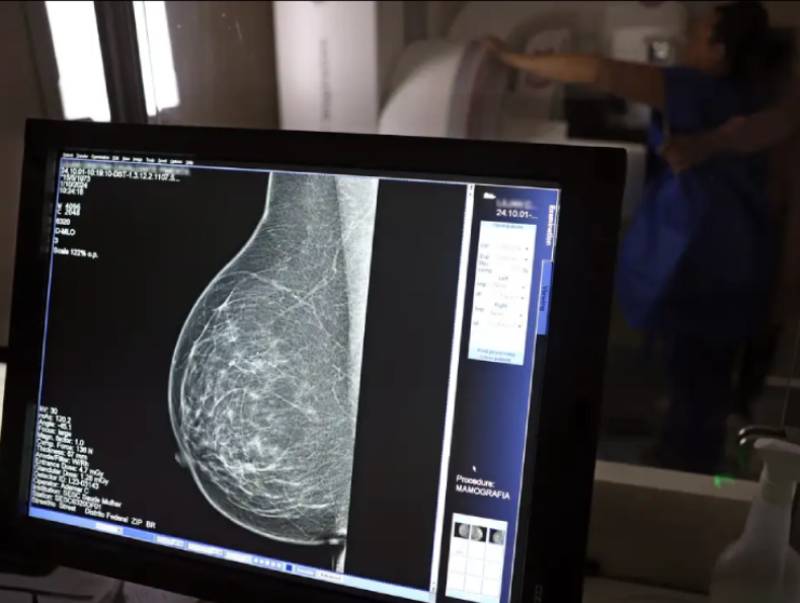

Ministério da Saúde passa a recomendar mamografia a partir dos 40 anos

24/09/2025 - Faixa de 40 a 49 anos concentra 23% dos casos de câncer de mama

O Ministério da Saúde passou a recomendar o acesso a mamografia, via Sistema Único de Saúde (SUS), para mulheres de 40 a 49 anos – mesmo que não haja sinais ou sintomas de câncer de mama. De acordo com a pasta, a faixa etária concentra 23% dos casos da doença, e a detecção precoce aumenta as chances de cura.

Até então, a orientação era que o exame fosse feito a partir dos 50 anos.